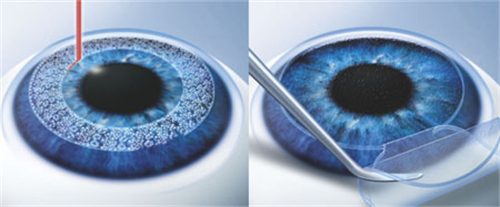

设备靠前,术前检查超全(OCT、角膜地形图等)。